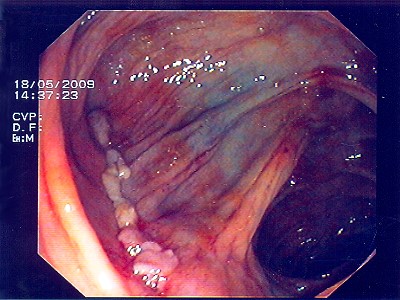

Nach einem speziellen kombinierten Manöver (laparaskopisch gestützte Koloskopie - gleichzeitige Bauch- und Darmspiegelung), gelingt es, den Polyp weit im Gesunden mit einem speziellen Klammernahtgerät zu entfernen, wobei die hier abgebildete Klammernahtreihe zurück bleibt. Der Eingriff erfolgt - wie gesagt - in so genannter Schlüssellochtechnik, aber auch mit unterstützender Darmspiegelung.